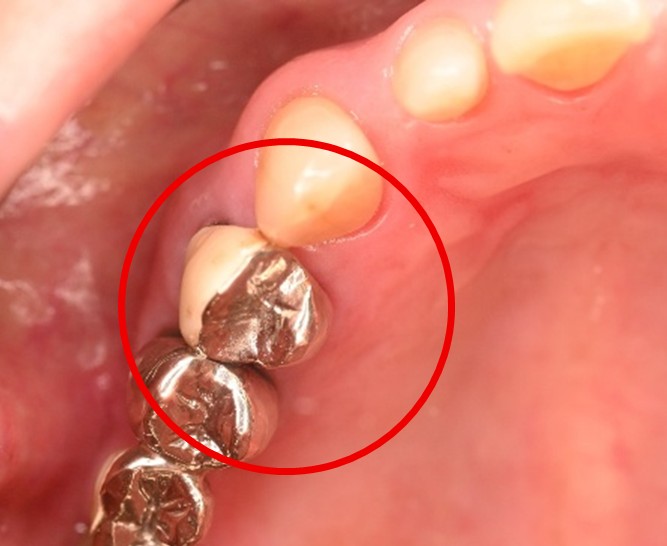

右下のブリッジがゆらゆら動く。

治療内容

ブリッジの支台になっている奥の歯が、被せ物の中で虫歯になり、支台の役割を果たさず、前方の歯のみで支えられていました。前方の歯をそのままにして、後方の部分を切り離すと、そのまま取れてきました。中は、虫歯で歯根しか残っていない状況でした。この歯は、根管治療後、単独でオールセラミック冠を被せ、歯のないところにインプラントを埋入しました。

Before

冠の中で大きな虫歯になり支台の役割を果たしていませんでした。

【インプラント埋入前】

冠はブリッジを切断しただけで取れてきました。軟化象牙質を取り除いたところ、歯根しか残っていない状況で保存できるかどうかのぎりぎりのところでした。

After